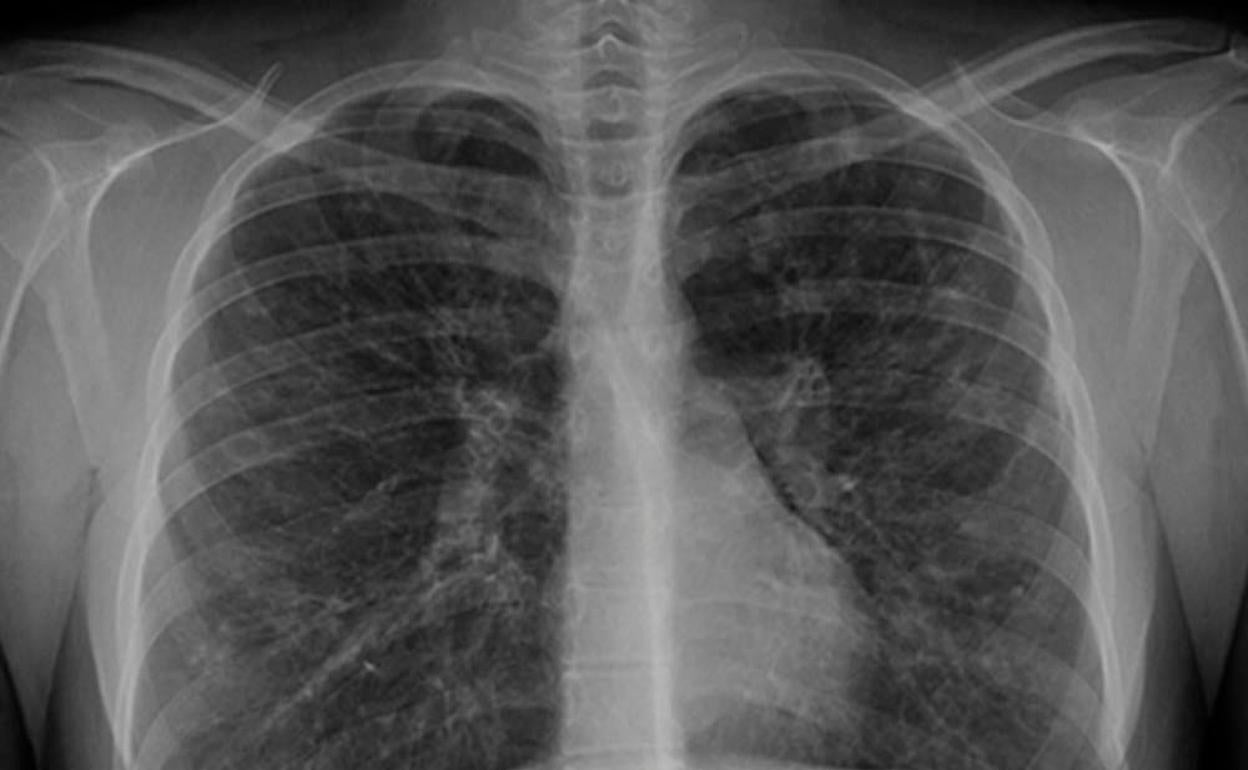

El Juzgado de lo Social número 2 de Bilbao ha condenado a Sidenor Aceros Especiales y Cofivacasa a indemnizar solidariamente con 311.438 euros, en concepto de daños y perjuicios, a un trabajador que sufre mesotelioma pleural por amianto.

Según ha informado en un comunicado la Asociación vasca de víctimas del amianto, Asviamie, el operario trabajó desde 1972 como laminador en Echevarria de Basauri hasta su prejubilación en 2003 y su jubilación definitiva en 2010. En 2018, en el Hospital de Galdakao, le diagnosticaron un mesotelioma epiteloide maligno, y en octubre, el Instituto Nacional de la Seguridad Social declaró su Incapacidad Permanente Absoluta derivada de enfermedad profesional.